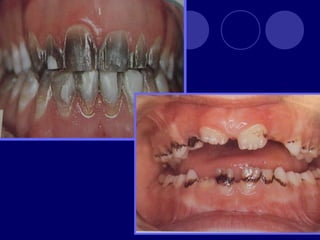

ANOMALÍAS DEL COLOR

TETRACICLINA:

 ERITROBLASTOSIS

 Amarillo verdosa

• 76.

ANOMALÍAS DEL COLOR PIGMENTACIÓN POR TETRACICLINA:  Gris marrón, amarillo  ERITROBLASTOSIS FETAL:  Amarillo verdosa